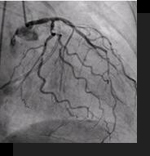

アンギオはカテーテルを使用し、X線画像を見ながら目的血管へ先端を送り、造影剤を使い撮影をする検査です。近年はこの検査技術を応用し、外科的手術に比べ苦痛の少ない治療もおこなえます。

当院でも血栓を溶解する治療、逆にコイル等を使用して塞栓をする治療や、バルーンやステントを用い血管の狭窄部位を広げる治療をおこなっております。

2014年10月より稼動している当院のX線循環器システム(アンギオ装置)は、DTS(Dose Tracking System)を搭載しています。

DTSとは、患者の身長・体重・透視や撮影におけるX線の照射情報から、患者モデルに対して皮膚線量を積算し、検査中においてリアルタイムに被曝部位を表示するシステムです。これにより、より少ない放射線被ばくでより良い検査を施行しています。

これは冠動脈CTと心筋シンチグラフィーの画像を重ね合わせたものです。狭窄している冠動脈により心筋の血流が低下しているのを1つの画像で見る事が出来ます。

※このCT画像はSPECT-CTのCTではありません。